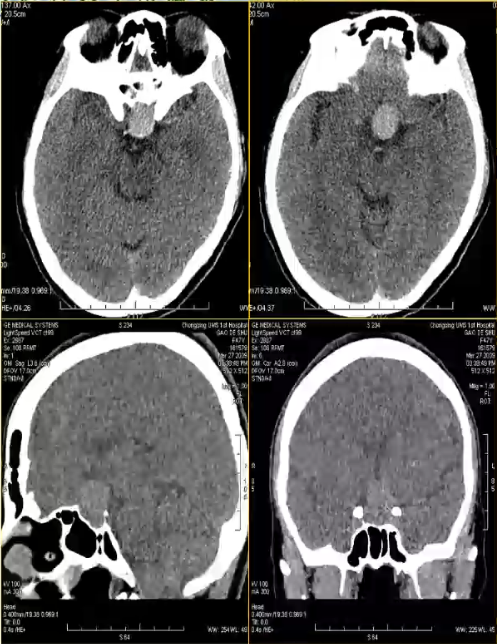

女,47岁,视力下降3月,CT平扫鞍区及鞍上高密度肿块,考虑垂体瘤,不除外动脉瘤,MRI垂体显示正常病变呈流空信号,增强后中心片状强化,病变的相位方向明显搏动伪影,VCTDSA清晰显示左侧颈内动脉床突上段动脉瘤